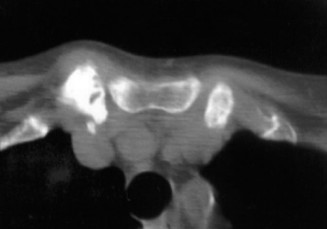

Thorough pre-operative planning begins with advanced imaging. While the initial ED evaluation mandates true orthogonal radiographs (AP and Axillary views) to confirm joint concentricity and rule out fractures, definitive surgical planning requires cross-sectional imaging. Magnetic Resonance Imaging (MRI), preferably an MR Arthrogram with intra-articular gadolinium, is the gold standard for evaluating the soft tissues. It allows for the precise identification of Bankart, ALPSA, and SLAP lesions, assesses the volume and integrity of the capsular tissue, and evaluates the rotator cuff.

To accurately quantify bipolar bone loss, a non-contrast 3D Computed Tomography (CT) scan with digital subtraction of the humeral head is mandatory. Glenoid bone loss is calculated using the "best-fit circle" method on the en face sagittal view of the glenoid. The width of the inferior glenoid is compared to the expected diameter of the intact posterior rim. Simultaneously, the Hill-Sachs lesion is evaluated to determine if it is "on-track" or "off-track." The glenoid track is calculated as 83% of the intact glenoid width, minus the measured anterior glenoid bone loss. If the medial margin of the Hill-Sachs lesion extends medial to this track, it is deemed "off-track" and will engage the anterior glenoid rim during abduction and external rotation, necessitating either a Remplissage or a Latarjet.

Clinical & Radiographic Imaging Archive